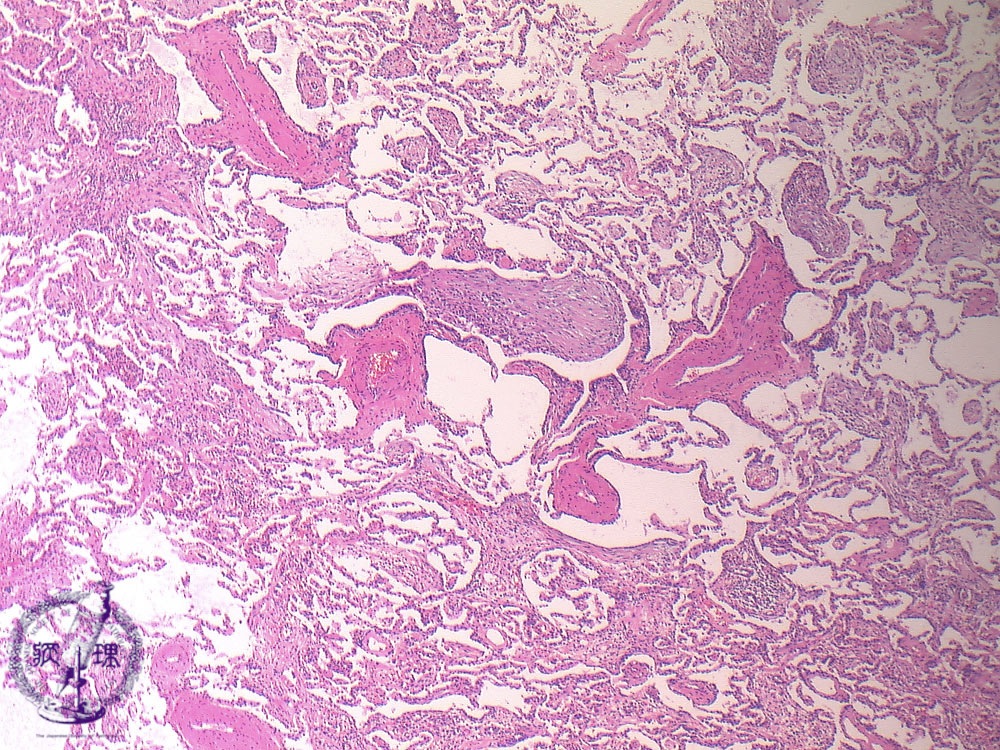

• (12)Interstitial pneumonia(cryptogenic organizing pneumonia (COP)/ Bronchiolitis obliterans organizing pneumonia (BOOP))

Microscopic view (HE stain, low power view): Polypoid granulation tissue fills alveolar ducts and spaces. Lymphocytes are seen infiltrating the interalveolar septum and surrounding bronchioles.